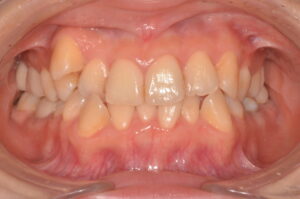

Before

After

| 主訴 | 歯並びを治したい |

| 診断名 | 叢生(混雑した歯並び) |

| 年齢・性別 | 82歳、女性 |

| 治療期間・回数 | 4ヶ月間、来院回数4回 |

| 治療方法 | 歯と歯の間に0.5mmのやすりがけをして歯の横幅を修正し、マルチブラケット装置(ワイヤー矯正器具)にて歯を配列 |

| 費用 | 検査料 55,000円 基本矯正料 220,000円 処置料 5,500円 / 月 |

| デメリット・注意点 | 唇に装置が当たって口内炎になる可能性 歯根吸収の可能性 調整のたびに2〜3日程度、上下の歯が接すると痛みが生じる |